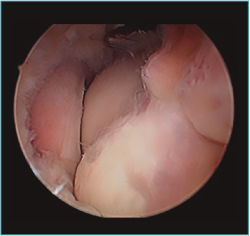

Figura 10. Mismo caso que en las Figuras 8 y 9 después del trabajo óseo. Obsérvese la recreación y fusión de ambas fosas radial y coronoidea con el típico aspecto de “tobogán” después del fresado de la cara anterior del húmero y la disminución de la altura de la coronoides. Todavía no se ha procedido a realizar la capsulectomía.